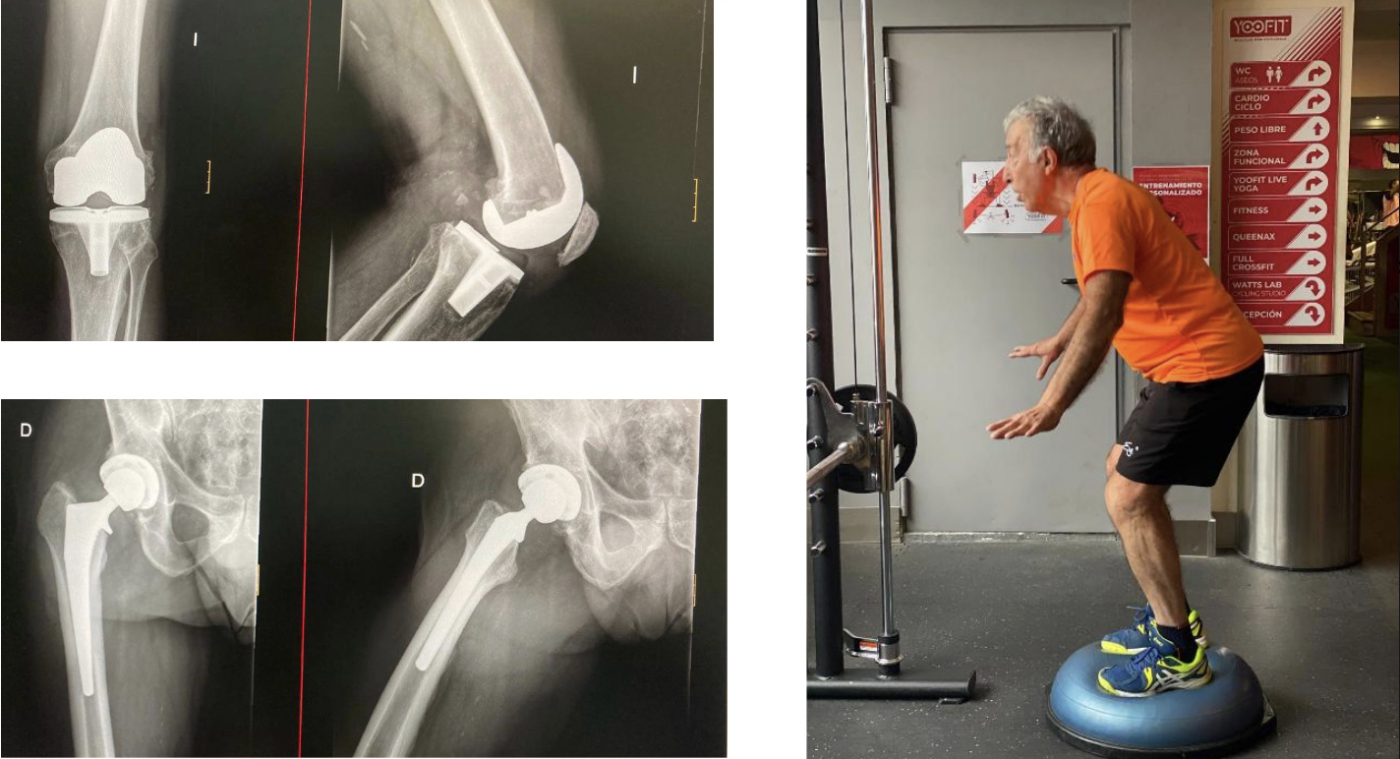

De las prótesis a una vida activa. Agustín

Agustín, a pesar de su avanzada edad y de contar con prótesis de rodilla y cadera, demostró que con compromiso y constancia se puede lograr mucho más de lo que parece. Gracias a nuestro programa de readaptación de lesiones, hoy entrena con seguridad, mejora su estabilidad y disfruta de una vida normal y activa.

No importa la edad ni las limitaciones: con el enfoque correcto, tú también puedes recuperar movilidad, fuerza y calidad de vida.